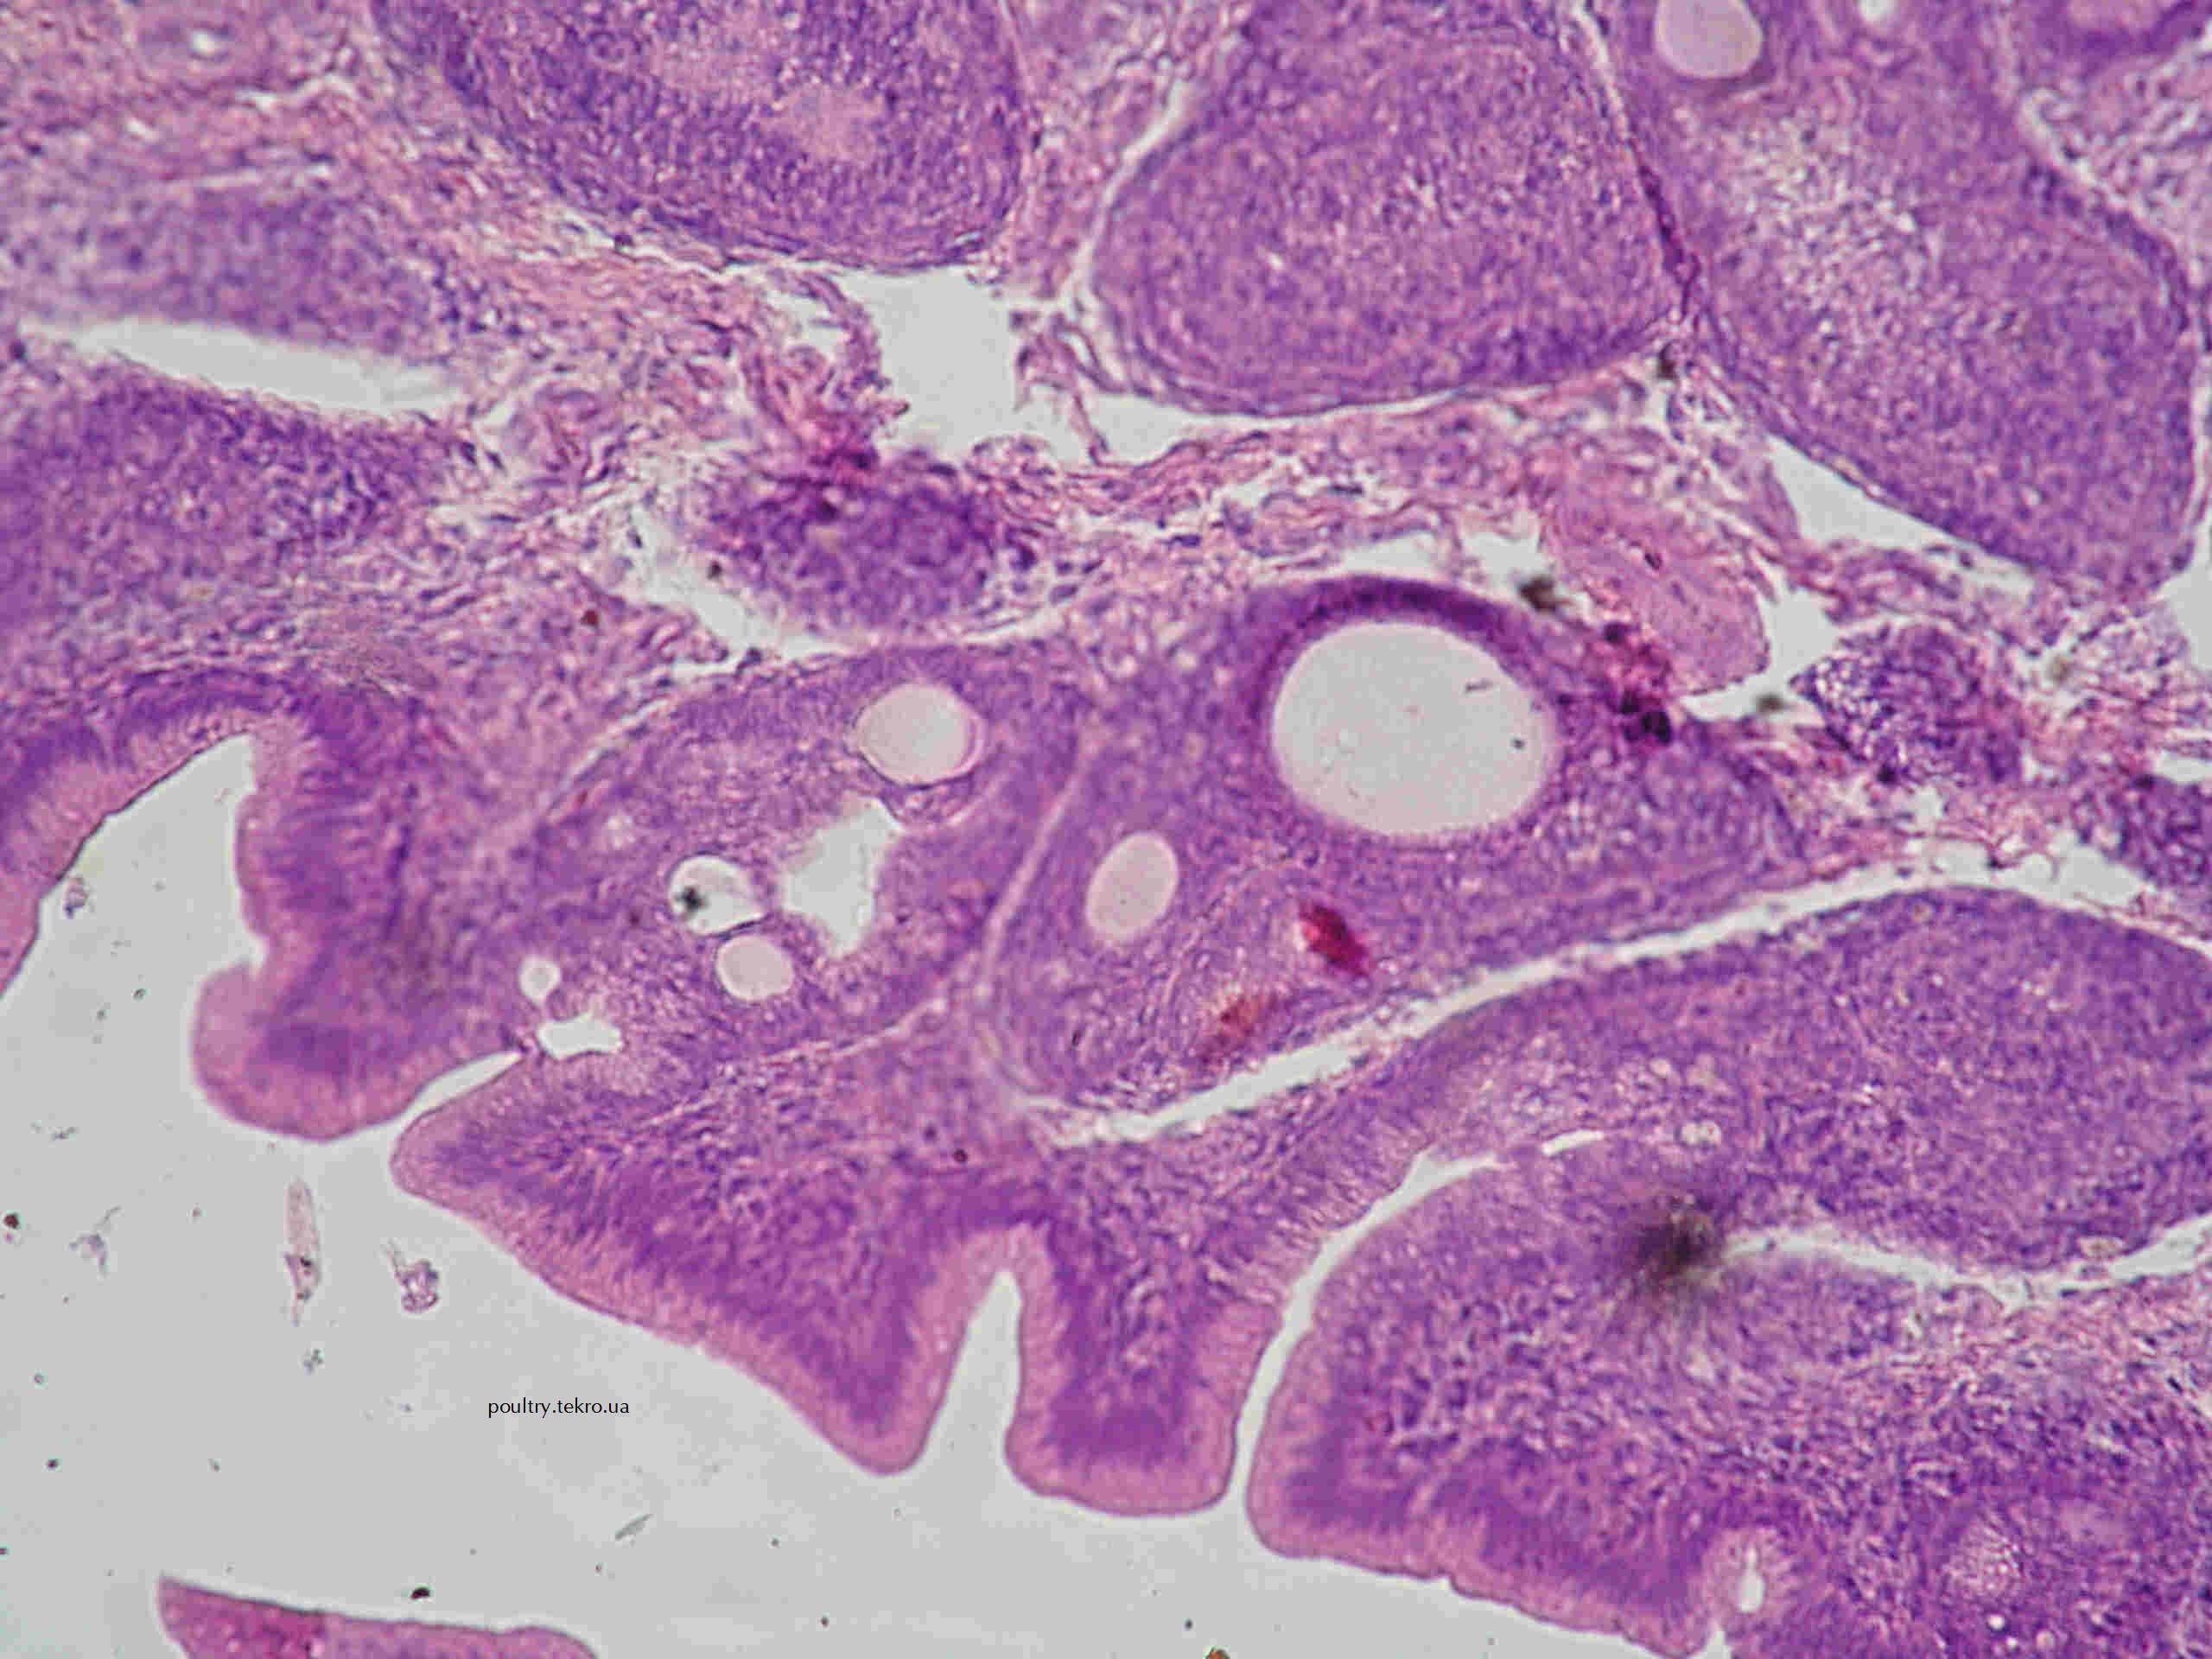

При хворобі Марека уражаються органи імунної системи. Клоакальна сумка може бути зменшена в розмірі або атрофована, в окремих випадках у ній формуються пухлиноподібні розростання. Лімфоїдні вузлики клоакальної сумки атрофуються, а на їх місці формуються кістозні порожнини. При цьому міжфолікулярні сполучнотканинні перегородки потовщені і інфільтровані лімфоїдними клітинами. На ранніх стадіях захворювання пухлинні вогнища формуються периваскулярно в міжфолікулярних сполучнотканинних перегородках в одній або в декількох складках слизової оболонки. З часом, при збільшенні пухлинних вогнищ лімфоїдні вузлики атрофуються або інфільтруються пухлинним проліфератом і зливаються (заміщуються) неопластичною тканиною. Проте, найчастіше у клоакальній сумці спостерігають гіпоплазію, аж до атрофії лімфоїдних вузликів і утворення на їх місці великих кістозних порожнин.

Рис. 14. Некрози у центральних ділянках лімфоїдних вузликів клоакальної сумки. Міжфолікулярна тканина інфільтрована лімфоїдними та гістіоцитарними клітинами. Кисти у лімфоїдних вузликах. Гематоксилін та еозин. х 100